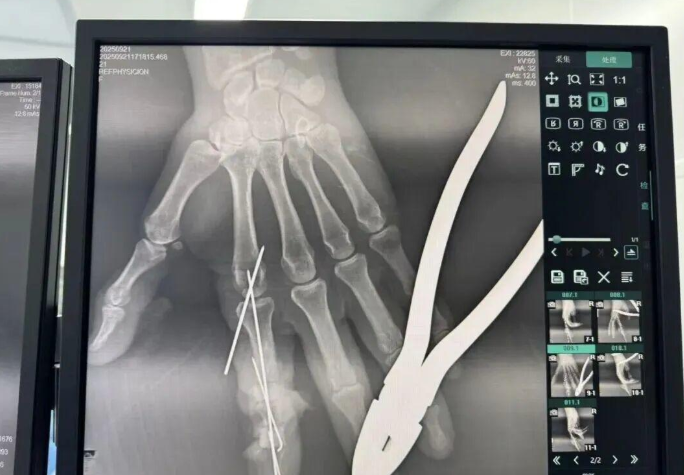

為確保手術(shù)成功,楊志主任特別聯(lián)合劉金海主任組成多手術(shù)組協(xié)作團(tuán)隊,充分發(fā)揮梯隊配合優(yōu)勢,反復(fù)研討后確定了“組合式”手指再造方案:利用右足踇趾的皮瓣、末節(jié)甲床及部分趾骨,聯(lián)合第二趾的趾間關(guān)節(jié),再取部分髂骨進(jìn)行精確植骨,將這些組織精密拼裝,重建一個兼具良好外形和功能的新示指。

多手術(shù)組協(xié)作,40倍顯微鏡下的“精微繡花”

手術(shù)當(dāng)天,多手術(shù)組梯隊配合的優(yōu)勢得到充分體現(xiàn)。無影燈下,楊志主任與團(tuán)隊各司其職、緊密配合,一場漫長的生命接力就此展開。在放大40倍的專業(yè)手術(shù)顯微鏡下,醫(yī)生們開始了精細(xì)操作。楊志主任在術(shù)后解釋道:“患者需要吻合的血管直徑僅0.5-1.0毫米左右,末節(jié)手指的毛細(xì)血管更是細(xì)如發(fā)絲。我們必須將移植組織與手部的血管、神經(jīng)、肌腱進(jìn)行精準(zhǔn)吻合,確保移植組織通血成活。這不僅要求醫(yī)生有扎實的顯微外科技術(shù),還要具備專業(yè)的整形外科審美能力,才能讓再造的指尖既好用又好看?!?/p>

手術(shù)中團(tuán)隊發(fā)現(xiàn),由于葉女士患有多年的內(nèi)分泌系統(tǒng)疾病,其血管質(zhì)量不佳,存在血管內(nèi)膜分層、動脈頑固性痙攣等挑戰(zhàn)。面對這一情況,團(tuán)隊及時啟動應(yīng)急預(yù)案。“每一根血管的吻合都不能有絲毫偏差,稍有不慎就可能出現(xiàn)血管內(nèi)血流不暢,從而導(dǎo)致移植組織壞死?!睏钪局魅窝a(bǔ)充道。